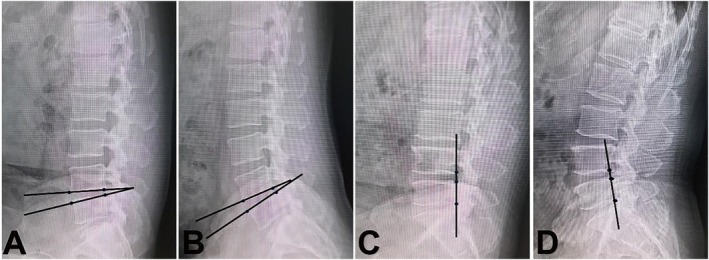

Methods: Between August 1, 2018, and December 1, 2020, a total of 316 consecutive cases underwent endoscopic decompression for LSS following conservative treatment. Based on specific selection criteria, 176 of these cases were retrospectively included in this study. The minimally invasive decompression was performed using a percutaneous uniportal and lateral interlaminar endoscopic approach under local anesthesia. This endoscopic procedure involved comprehensive decompression of the central canal and unilateral recess, addressing the lamina, hypertrophic ligamentum flavum (LF), and medial osteophytes of the facet joint. Clinical outcomes were assessed using the single continuous walking distance (SCWD) without pain, the modified MacNab criteria, the Oswestry Disability Index (ODI), and the visual analogue scale (VAS). Radiographic changes, both preoperative and postoperative, were documented and analyzed. This analysis included evaluating the stability of the lumbar spine through lumbar hyper-flexion and hyper-extension X-rays, as well as determining the lumbar canal cross-sectional area (CCA) using CT scans.

Results: The mean follow-up period was 47.4 ± 7.1 months. The average operative duration was 65.3 ± 12.6 min, and the mean estimated blood loss was 10.4 ± 8.5 mL. The average length of postoperative hospital stay was 2.2 ± 1.3 days. There was a significant improvement in SCWD without pain (p < 0.05). Postoperatively, the ODI and VAS scores for both back and leg pain showed significant reductions (p < 0.05). Based on the modified MacNab criteria, the overall rate of good-to-excellent outcomes was 95.45%. The CCA increased significantly from 52.0 ± 11.0 to 122.5 ± 12.1 mm2 (p < 0.05). The stability of the spine did not exhibit significant changes compared to the preoperative state.